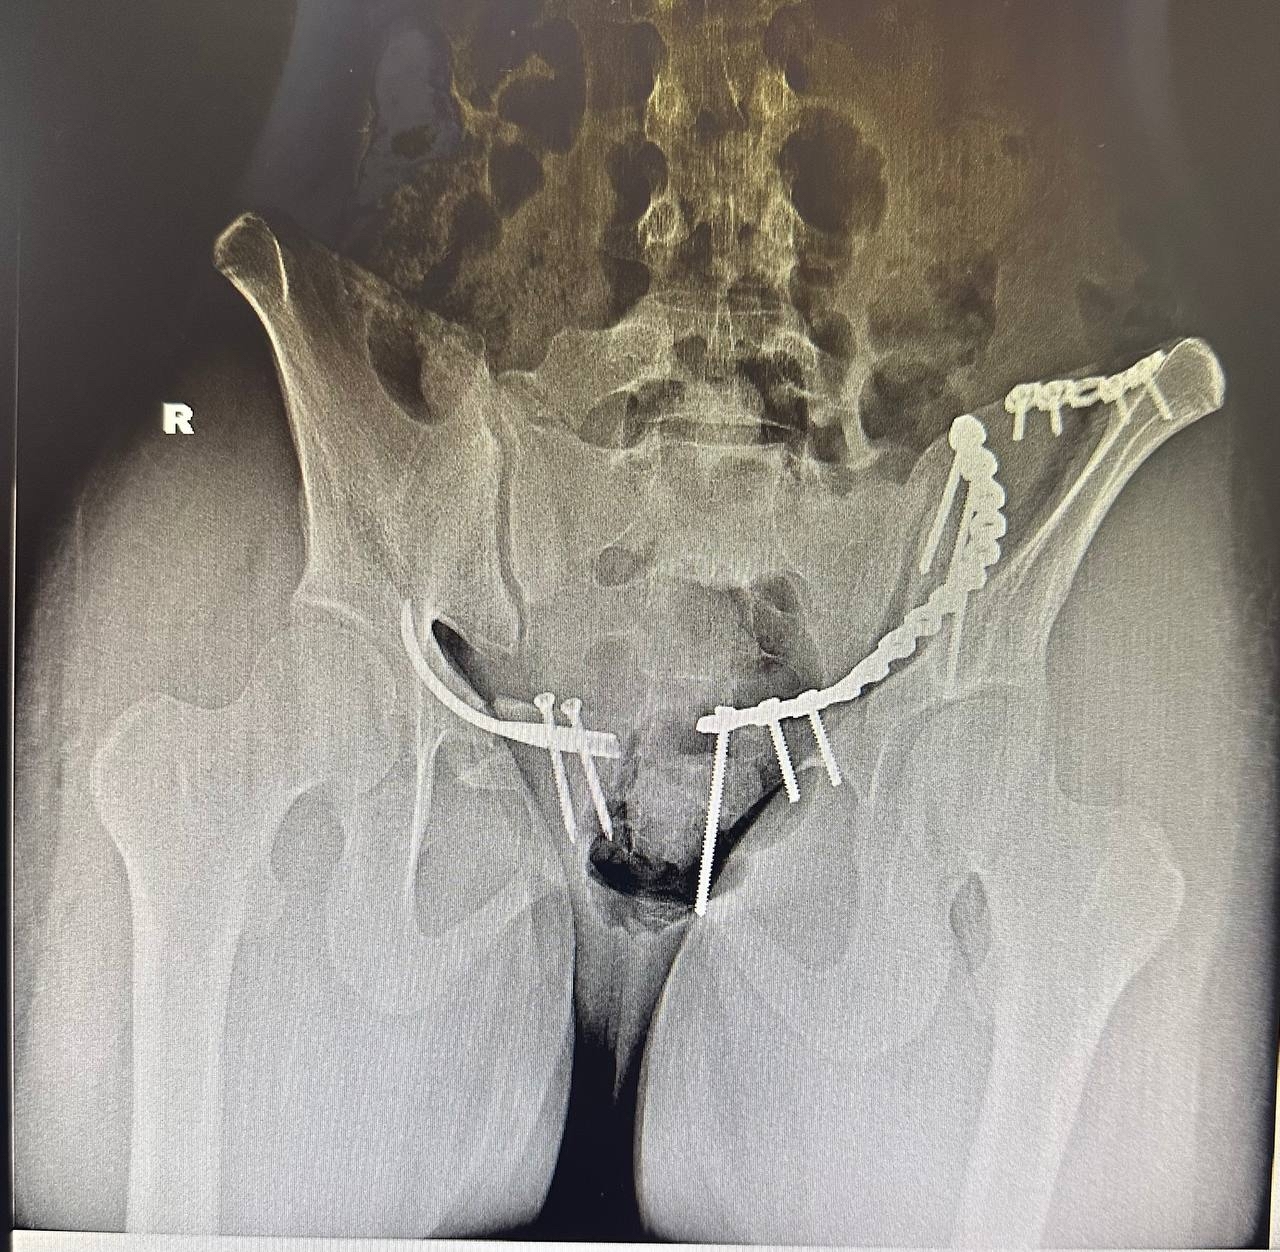

Как сообщили в пресс-службе медучреждения, девушка была переведена из центральной районной больницы с диагнозом: закрытая травма таза, перелом лонной кости справа, нестабильный перелом крыла подвздошной кости слева с нарушением целостности тазового кольца, а также шок 1-2 степени.

После стабилизации состояния пациентке в ходе одной операции выполнили два вида остеосинтеза: интрамедуллярный блокируемый малоинвазивный остеосинтез лонной кости справа и накостный остеосинтез крыла подвздошной кости слева. Хирургическое вмешательство позволило восстановить опороспособность таза.